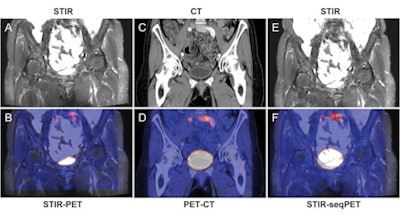

Bladder of a 65-year-old female patient. Images illustrate improved alignment with simultaneous PET/MRI (A, coronal STIR; B, fused images) compared to sequential PET/CT (C, coronal CT; D, fused images) and retrospective fusion of PET and MRI (E, coronal STIR; F, fused images). Images courtesy of Radiology.For all thoracic regions, the amount of misalignment was similar, according to Brendle and colleagues. Mean cumulative misalignment was 10.1 mm (± 7.7) in the right lung, 11.0 mm (± 8.4) in the left lung, and 12.0 mm (± 9.2) in the mediastinum.